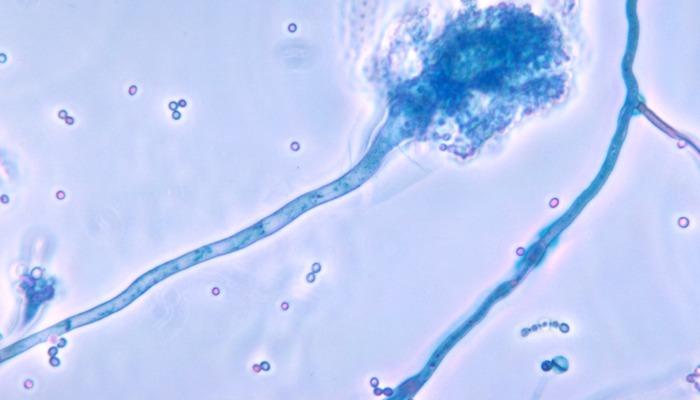

Birleşik Krallık’ta korkutan araştırmalar! Ölümlü mantar hastalıkları küresel ısınma ile Avrupa ve Asya’da yayılabilir